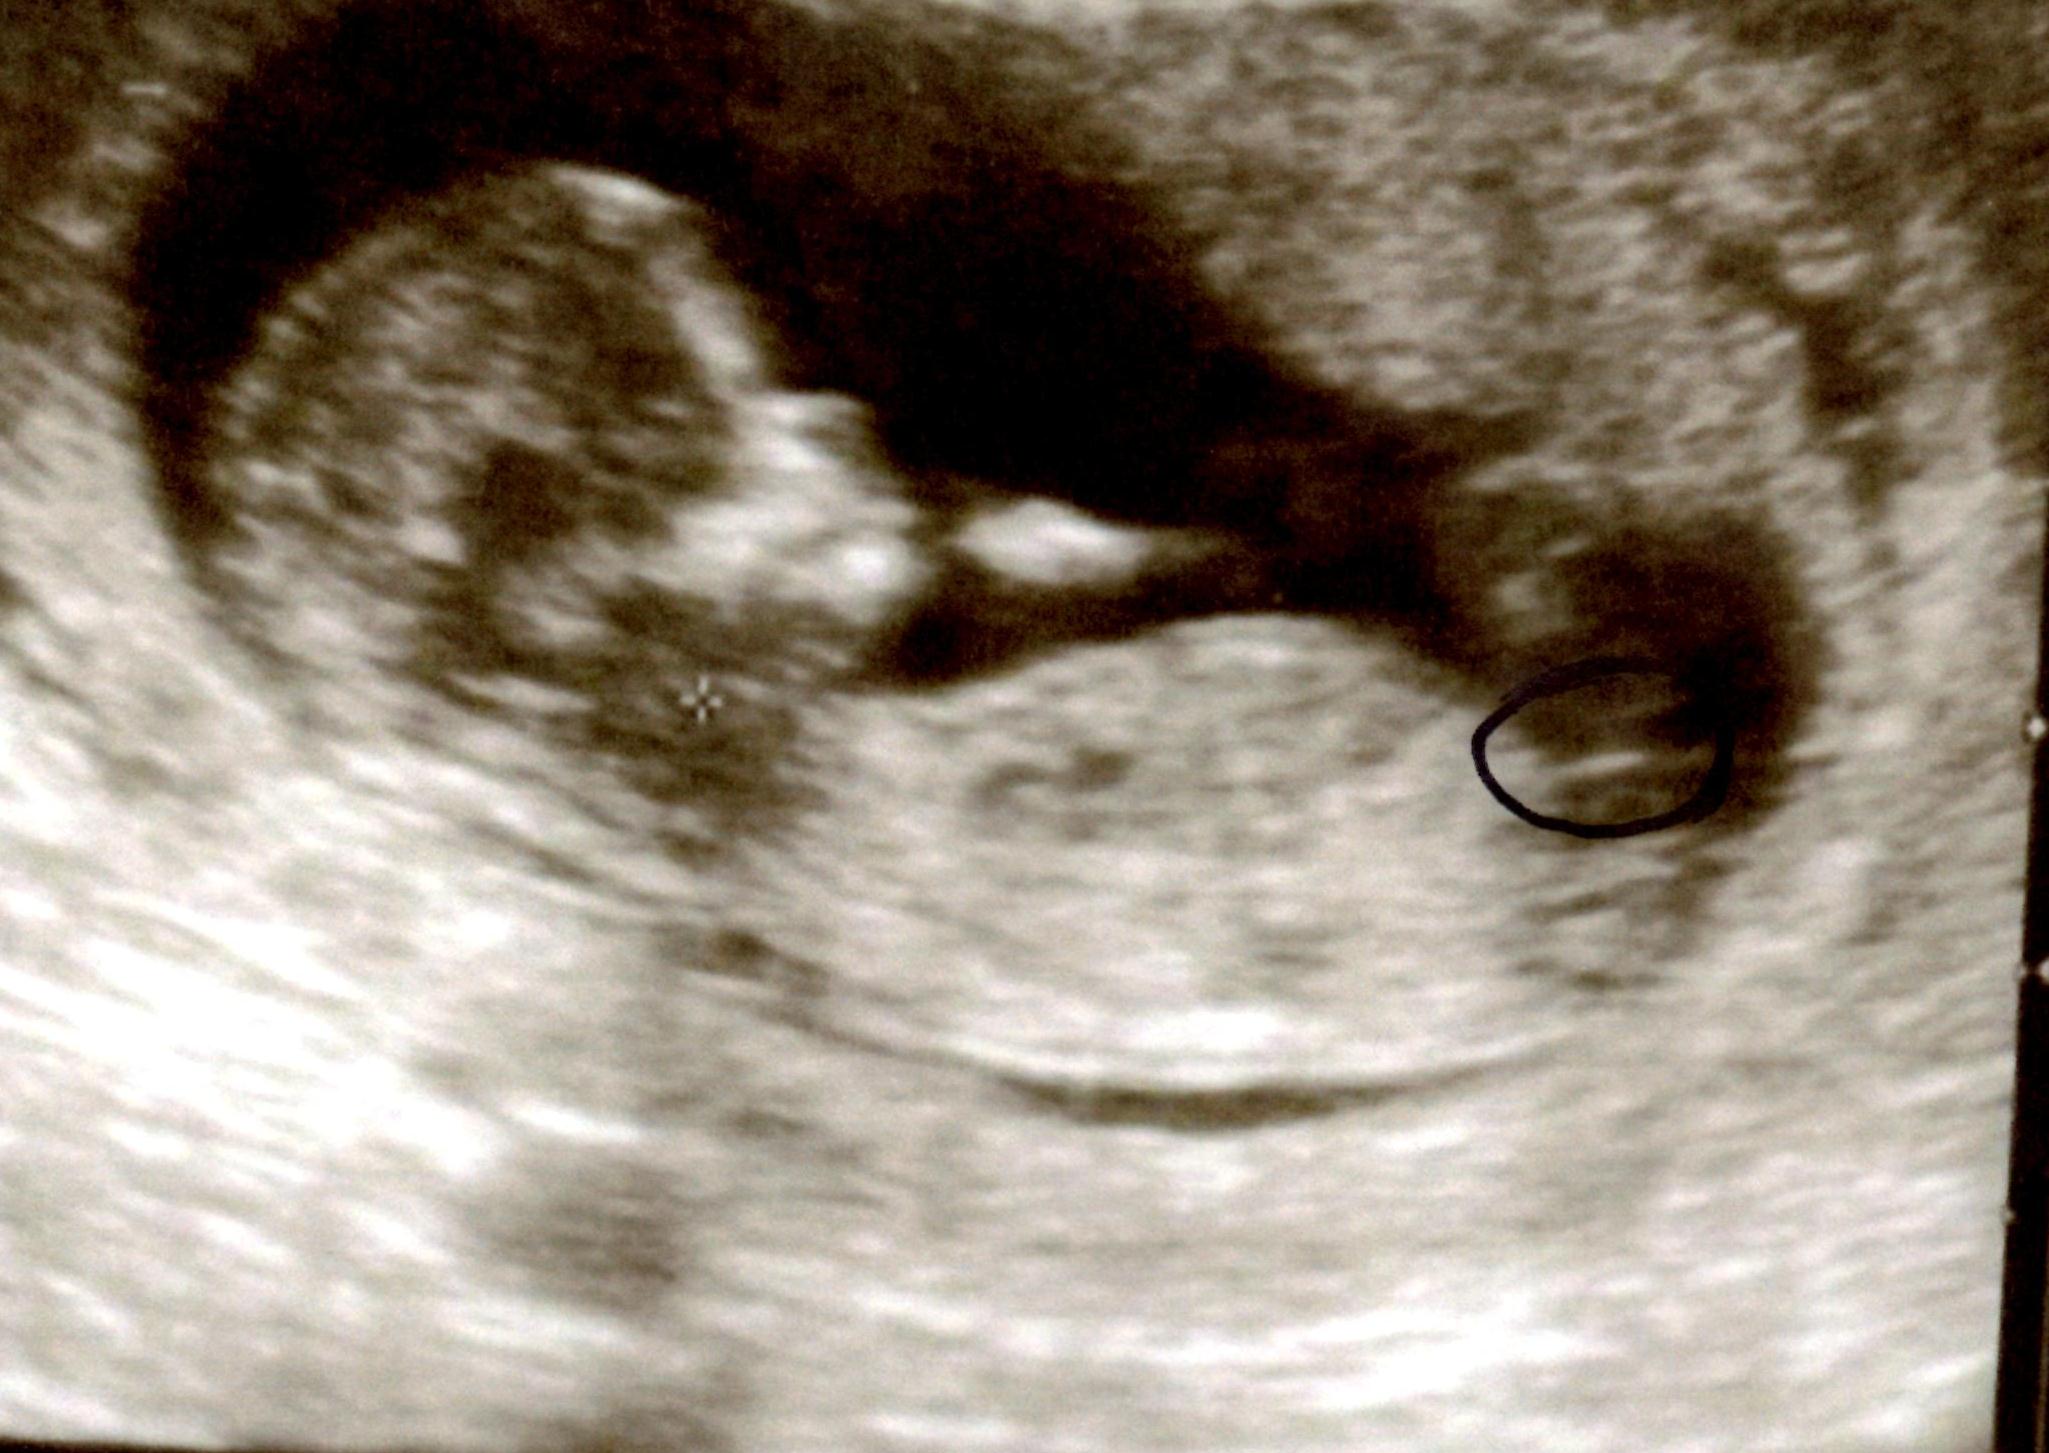

Looking for some hope that is could be a girl ... but thinking it is looking like boy number 4 for me?!!

If that's the nub just seems to look slightly angled.

Nub is totally flat :XX:

ever so slightly tilted upward but at only 12 or 13 weeks i wouldn't expect a huge tilt. leaning team blue over here.

It looks pretty long and flat but I don't know. There is something a bit not-quite-girl still. I'd lean girl though.

Girl lean..if we're seeing the WHOLE nub. Even if I saw the whole thing...the whole bump on the end or how forked is forked enough has me seeing circles. Good luck!

we are not seeing the full nub. Boy nubs can have that white flat line at the bottom as well.....and I also see a shadow above the white line, but it could be anything.... I really think its 50/50 based on this picture x